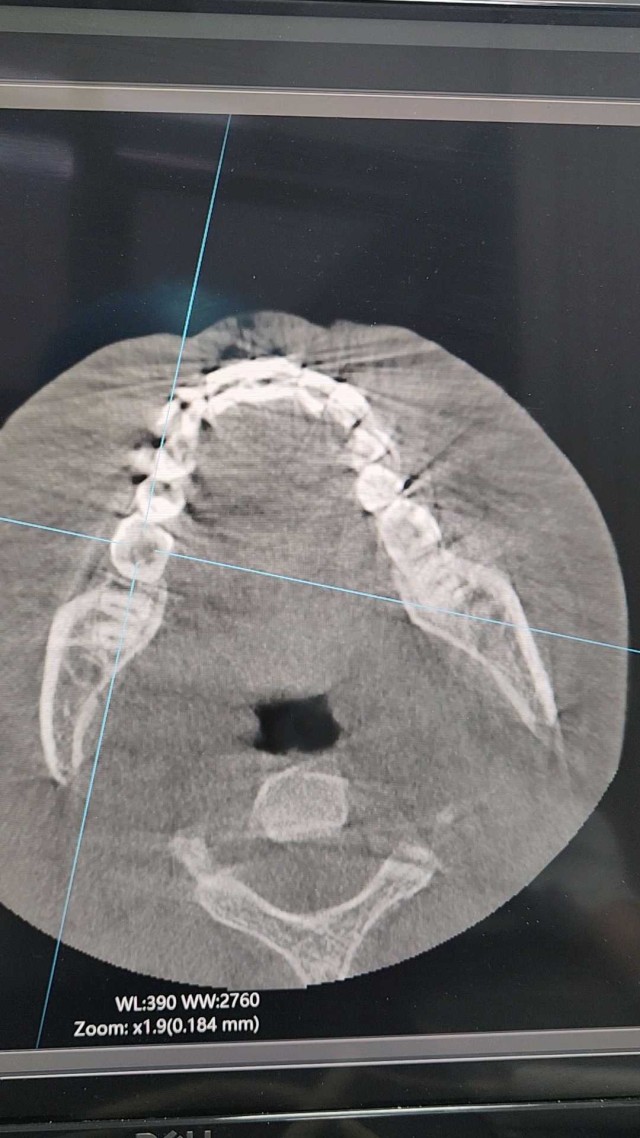

拔牙后骨内高密度物是什么

如题,科室常规拔牙后会填塞明胶海绵止血,复杂的还会沾碘仿颗粒。所以,有的患者拔牙后很长时间了,牙槽窝内出现了高密度的影像,因为不适或者种植前,我们打开过一些,发现就是粉状或者散碎的颗粒,不像骨片或者牙片,虽然这种患者不多,但是有因为这个引起纠纷的,请问大家这个是什么,有遇到过类似情况的么,谢谢大家解惑。图1是4个月的患者,图2是1年的患者。